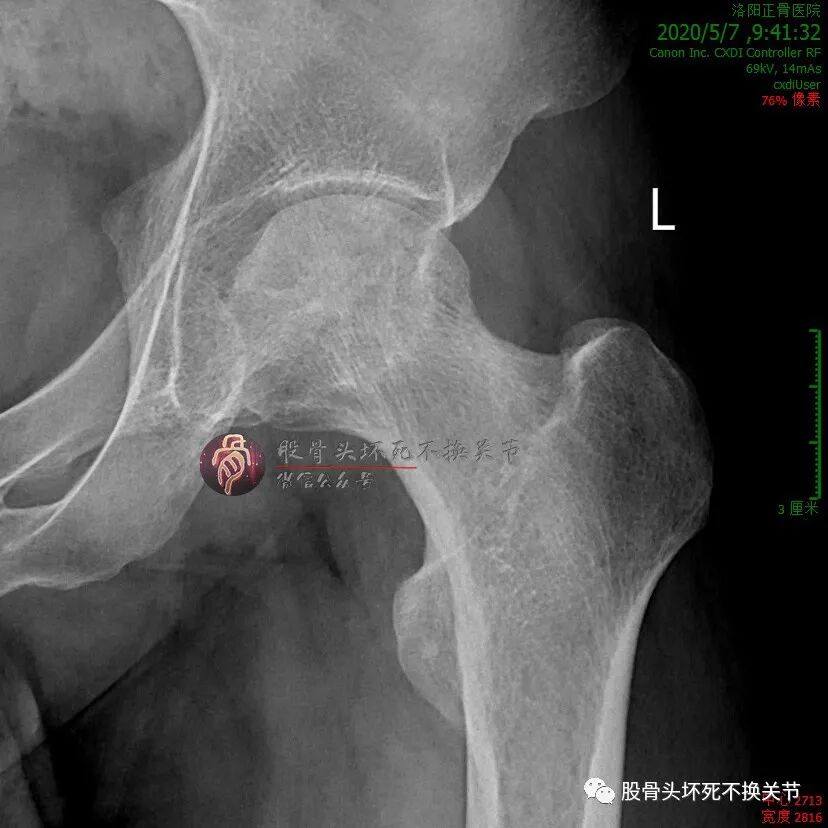

初次就诊2年后:

不错嘛,在工作、生活没耽误的前提下,病人偶尔来医院复查或治疗,也没有想象中的那么不便。初次就诊近3年复查:

这股骨头杠杠的!